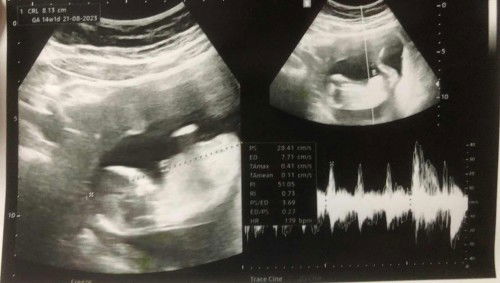

ตรวจโครโมโซมตอนอายุครรภ์ 10w3d รอผล 7 วัน ความเสี่ยงต่ำทุกคู่ อิแม่ใจฟูมากก ตอนผลยังไม่ออกกลัวเสี่ยงแล้วได้เจาะน้ำคร่ำ #ท้องแรกได้ลูกชายค่ะ ไม่แพ้เลยตั้งแต่เริ่มตั้งท้องมีแค่ง่วงและเพลีย ขอเสียงแม่ๆทีมเดียวกันหน่อยจ้า 😊